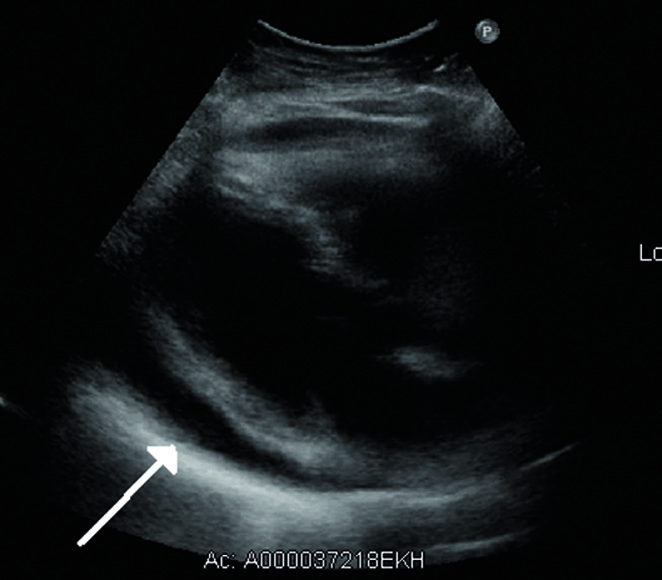

• Echokardiographie: Schneller und empfindlicher Ergussnachweis ab 50 ml (echofreier Bereich hinter dem Herzen, bei größerem Erguss auch vor dem Herzen). Bei Perikardtamponade Kollaps des rechten Vorhofs und Kompression der rechten Herzkammer.

Echokardiographisch lässt sich die Flüssigkeitsansammlung im Herzbeutel sehr deutlich darstellen. © wikimedia/James Heilmann.